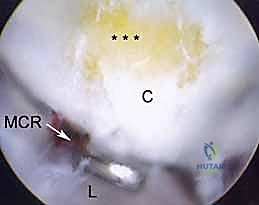

1. The Midcarpal Radial Portal (MCR)

- Location: Approximately 1 cm distal to the 3-4 portal. It is bounded radially by the ECRB tendon and ulnarly by the EDC tendons.

- Anatomy: This portal enters the midcarpal joint, providing a view of the scaphoid, lunate, capitate, and hamate articulations.

- Neurovascular Risks: Generally safe, but the superficial radial nerve branches can be in the vicinity more radially.

- Function: A primary viewing portal for midcarpal arthroscopy, allowing triangulation with the midcarpal ulnar portal for instrumentation. Essential for probing the SLIL and LTIL joint spaces for instability and assessing chondral lesions.